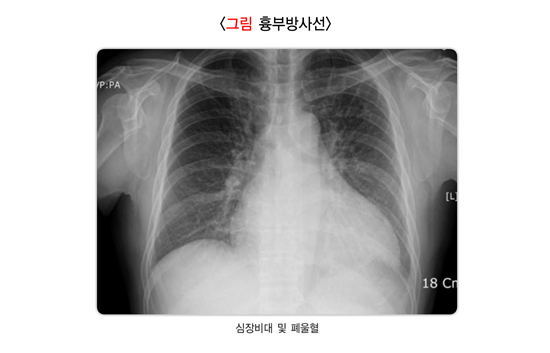

활동할 때 숨이 가쁘거나 가슴이 아프며, 두근거리기도 합니다. 자주 피로를 느끼고 때로는 어지럽거나 기절할 수도 있습니다. 증상이 점차 심해지면 각혈, 전신 부종, 색전증(뇌졸중, 하지나 장의 색전증)도 나타날 수 있습니다.

평소에 증상이 가볍다가 급격히 악화되기도 하고, 첫 증상으로 급성 호흡곤란이나 폐부종이 발생할 수 있습니다. 심근경색증, 심내막염, 대동맥 박리증, 외상 등에 의한 심장 판막 질환일 때는 증상이 갑자기 나타나는 경우가 많습니다.